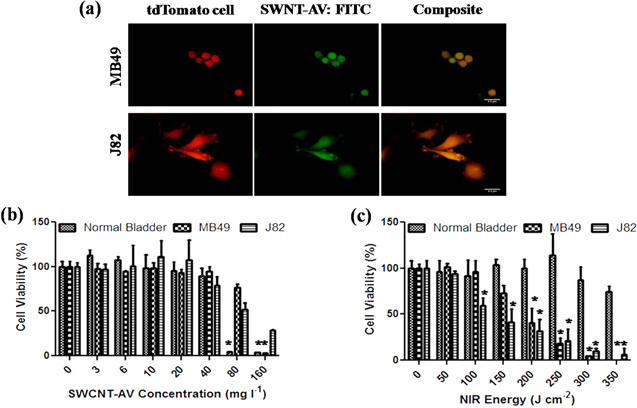

The dissociation constant of AV binding to MB49-Td-Luc and J82-Td cells was 4.14 ± 1.30 nM and 0.38 ± 0.20 nM, respectively, confirming a strong affinity of AV for bladder tumours. Once AV and PS interaction was confirmed, further evaluation of SWCNT-AVs conjugate binding affinity was visualised via fluorescence microscopy. As seen in figure 3(a), even after the conjugation of SWCNTs to AV, AV still strongly associated with mouse as well as human bladder cancer cells.

Figure 3. In vitro binding specificity and SWCNT-AV and NIR tolerance. (a) Fluorescence imaging confirming SWCNT-AV binding to murine (MB49) and human (J82) bladder cancer cells. TdTomato transinfected MB49 and J82 cells (left), FITC labelled SWCNT-AVs (middle), and composite (right). Scale = 3.2 μm. Murine and human bladder cancer lines as well as normal bladder progenitor cells were tested to determine tolerance to (b) SWCNT-AVs and (c) NIR energy. Data is presented as mean ± SE (n = 3). Statistical significance between groups is denoted by * (p < 0.01) with control, untreated samples compared against SWCNT-AV or NIR treated samples.

Standard image High-resolution imageTolerance of bladder cancer as well as normal bladder progenitor cells for SWCNT-AVs and NIR light was determined as seen in figures 3(b) and (c). SWCNT-AV concentrations above 40 mg l−1 were detrimental to normal bladder progenitor cells and to a lesser extent for MB49 and J82 cells. In order to ensure no damage to healthy bladder urothelium occurred due to SWCNT-AV toxicity, a conservative 20 mg l−1 concentration of nanotubes was used for all following work. Normal bladder progenitor cells had a higher tolerance to NIR energies with minimum cytotoxicity seen up to 350 J cm−2. Mouse (MB49) and human (J82) bladder cancer cell lines had noticeable decreases in viability at 150 J cm−2 and 100 J cm−2, respectively.

Bladder progenitor cells at 70% confluence were less tolerant to the SWCNT-AV conjugate (figure 3(a)). In previous work, we found that non-confluent endothelial cells express PS on the cell surface, but do not when they are confluent [28]. Others have shown that AV is internalised on cells expressing PS on the surface by a pinocytic pathway [29]. In addition, we have shown that SWCNTs with the F3 peptide attached are internalised in non-confluent endothelial cells, which results in a loss of viability over time [30]. Therefore, it likely that the non-confluent progenitor bladder cells were damaged by internalisation of the SWCNT-AV conjugate after binding to PS on the cell surface at the concentration of the conjugate used.